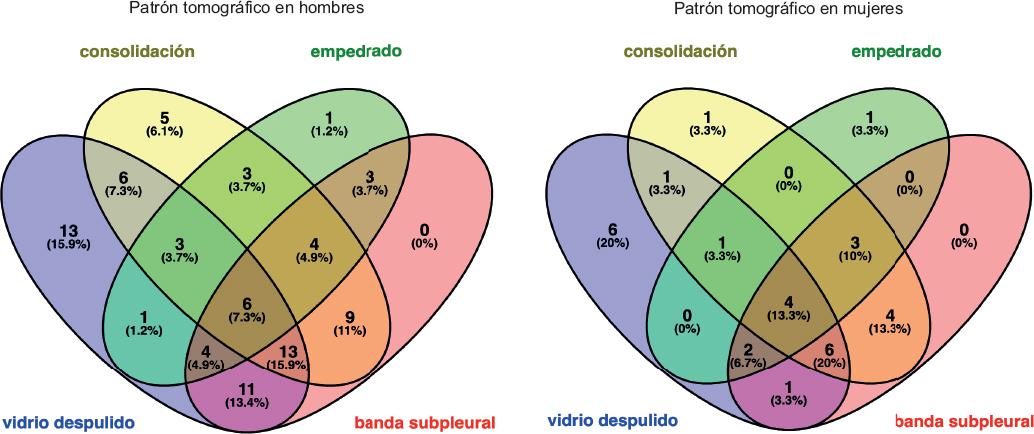

En la tomografía simple de tórax realizada al ingreso de cada paciente, los patrones más comunes fueron los siguientes: opacidad de vidrio esmerilado de predominio periférico y subpleural (Figura 1), encontrado en 15.9 % de los hombres y 20 % de las mujeres; la consolidación, con predominio hacia los segmentos posterobasales (Figura 2); así como los patrones de empedrado y mixto, forma concomitante de los mencionados (Figura 3). En los diagramas de Venn (Figura 4) se representan los porcentajes de las diferentes combinaciones de patrones.

Figura 4 Diagrama de Venn. Patrón tomográfico en hombres (derecha) y mujeres (izquierda) con neumonía causada por SARS-CoV-2. En el diagrama se muestra la combinación de los patrones por sexo; el número localizado en los sectores de cada óvalo indica la cantidad de pacientes que mostraron el patrón y la concomitancia con los otros patrones.

Confirmamos que el patrón de vidrio esmerilado de distribución subpleural y periférica se presentó en la mayoría de los casos y le siguió en frecuencia el patrón de consolidación, los cuales en pocas ocasiones se presentaron de forma aislada, tal como se muestra en la Figura 4 (diagrama de Venn); el patrón mixto (combinación de dos o más patrones) fue el tercero en frecuencia. En numerosos pacientes se observaron bandas subpleurales, las cuales, de acuerdo con la revisión bibliográfica, podrían sugerir bandas fibrosas en formación, que aparecen después de la fase aguda de la enfermedad.9 Sabemos que la fibrosis pulmonar puede ser una secuela del síndrome de dificultad respiratoria aguda y aunque el virus sea erradicado en pacientes recuperados de COVID-19, el desarrollo de fibrosis pulmonar es irreversible, por lo que se sigue especulando acerca de las consecuencias pulmonares a largo plazo de COVID-19 y no deben asumirse sin un estudio prospectivo adecuado.10 En cuanto a la distribución de las lesiones, confirmamos la afectación pulmonar bilateral y multifocal, lo que coincide con los resultados de investigaciones previas.